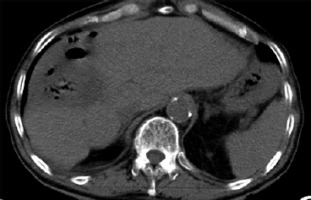

Three months after RL, the patient presented with fever and chills. Despite an infectious workup, imaging revealed a liver abscess secondary to a hepatocolic fistula (Figure 3). Intravenous antibiotics were administered, and a percutaneous drain was placed. Following a multidisciplinary team review, a right hepatectomy, fistulectomy, and colectomy were performed. Intraoperatively, a necrotic enteric wall with an abscess extending into the right liver lobe was identified. The patient was discharged on intravenous antibiotics 20 days after surgery with no signs of bacteremia.